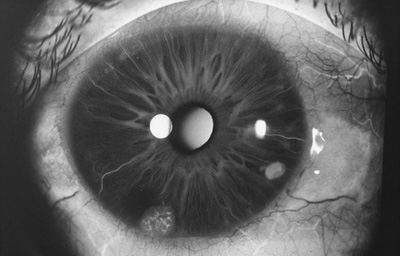

Nódulos de Lisch

Archivo Fotográfico Dr. Francisco Barraquer.

Nódulos de Lisch

Archivo Fotográfico Dr. Francisco Barraquer.

Hamartomas - Nódulos de Lisch. Son estructuras benignas, nodulares, de aspecto gelatinoso, implantadas con pedículo sésil sobre la superficie de la hoja anterior del Iris, compuestas por proliferación de células histológicamente maduras, de origen melanocítico normales del tejido en el que residen, de color que varía del castaño claro al castaño oscuro y generalmente de ± 1.0mm. Cuando se asocian a la Neurofibromatosis de Von Recklinghausen, se las considera patogneumónicas y se las denomina nódulos de Lisch (24, 25,26)